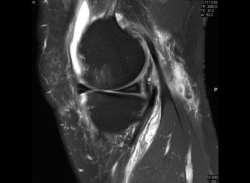

1.1. Meniscos

Se identifican como estructuras hipointensas en todas las secuencias, con asta anterior y posterior de morfología triangular.

La RM es la técnica de elección en el diagnóstico de la patología meniscal(17) (Figuras 30, 31, 32, 33, 34 y 35).

Figura 30. Corte de secuencia sagital T2 Fat-Sat de resonancia magnética de rodilla: menisco externo normal.

Figura 31. Corte de secuencia sagital T2 Fat-Sat de resonancia magnética de rodilla: menisco interno normal.